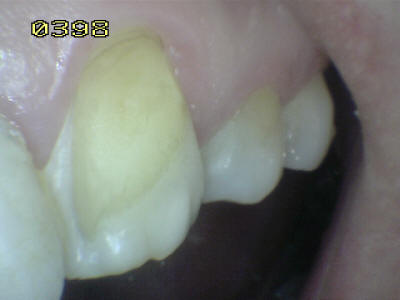

Paciente de sexo femenino de 60 años de edad, que a la inspección clínica se observa perdida de esmalte por erosión ácida en los dientes antero-superiores. Durante el interrogatorio el paciente cuenta que ingiere grandes cantidades de limón y naranjas naturales. Este habito dietético ocasiona erosión ácida por el contenido de acido cítrico que contienen dichas frutas.

Note en las imágenes inferiores el deterioro extenso del esmalte, que lleva en algunos sitios a la exposición de la dentina. Como el proceso es gradual el paciente no tiene sintomatología dolorosa al estímulo térmico.

Este tipo de lesión es clasificada en una escala de leve, moderada y grave, como grave y debe ser tratada con recubrimientos estéticos a base de resina o porcelana. El no tratar estas lesiones puene llevar a producir caries dentinaria con la pérdida de las piezas dentales. Otra acción a  tener en cuenta es la posibilidad de un cambio en la dieta, basado en la disminución de la frecuencia de la ingesta del limón y naranja.

Observe como se ha perdido la estructura dental en 13, 12 y  en 11 una carilla en resina compuesta  donde se ha deteriorado el borde cavo superficial de la misma. En 23 el mismo patrón de desmineralización dental